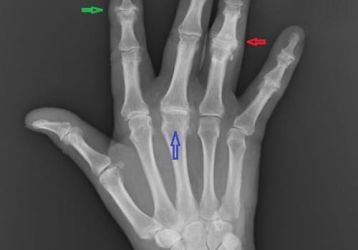

Узелки Гебердена и Бушара: симптомы, диагностика и лечение

Что представляют из себя узелки Гебердена и Бушара, почему и как развивается болезнь. Симптомы появления узлов, диагностика и методы лечения.